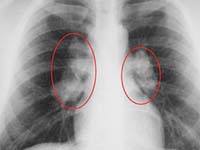

Характерные изменения при саркоидозе выявляются при рентгенографии легких, в ходе КТ или МРТ легких – определяется опухолевидное увеличение лимфоузлов, преимущественно в корне, симптом «кулис» (наложение теней лимфоузлов друг на друга); очаговая диссеминация; фиброз, эмфизема, цирроз легочной ткани. У более половины пациентов с саркаидозом определяется положительная реакция Квейма – появление багрово-красного узелка после внутрикожного введения 0,1—0,2 мл специфического саркоидного антигена (субстрата саркоидной ткани больного).